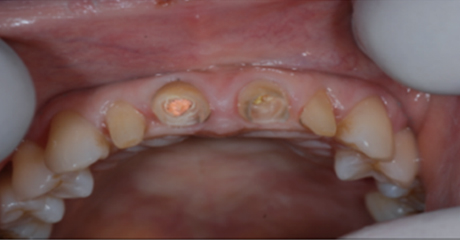

치아의 길이가 너무 짧은 경우는 치아의 길이를 늘리는 수술이 필요하기도 합니다.